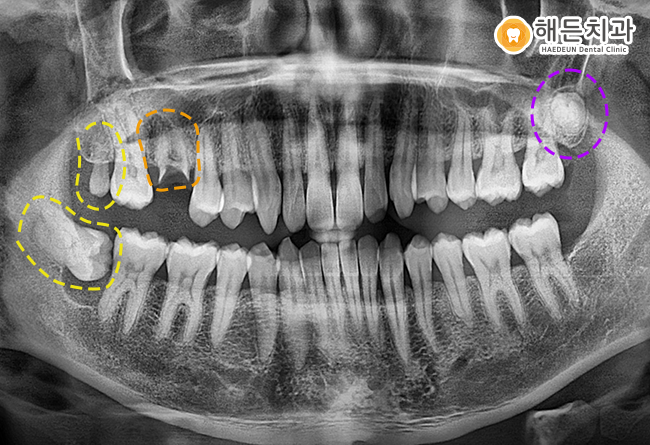

정밀한 검진을 위해 파노마라 사진을 촬영해 확인해보니,

현재 환자분의 구강 내에는 3개의 사랑니가 존재하고 있는 상태였습니다.

오른쪽 아래 사랑니는 완전히 기울어진 상태로, 구강 내 불편감을 주고 있는 상황이었으며,

오른쪽 위와 왼쪽 위의 사랑니는 다행히 크기가 작고 잇몸 위로 맹출되기 전이라, 환.자분께서 따로 불편감은 느끼지 않으신 상태였습니다.

우선은 불편감을 가지고 있는 오른쪽 아래 사랑니를 발치하면서

오른쪽 위의 사랑니와 주황색 표시의 뿌리만 잔존해있는 치아를 함께 발치를 도와드리기로 했습니다. 😊

사랑니의 위치 및 방향, 인접치와의 관계, 신경관의 위치 등

구강 내 상황을 면밀하게 파악한 후, 사랑니 발치 및 잔존치근 발치를 진행하였습니다.